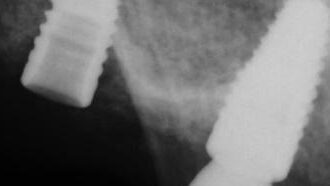

A Fractured Abutment Screw Case Initially Attempted With a Generic Recovery Kit and No Microscopic Visualization – 0035

This case exemplifies a fractured abutment screw case initially attempted with a generic recovery kit and no microscopic visualization.